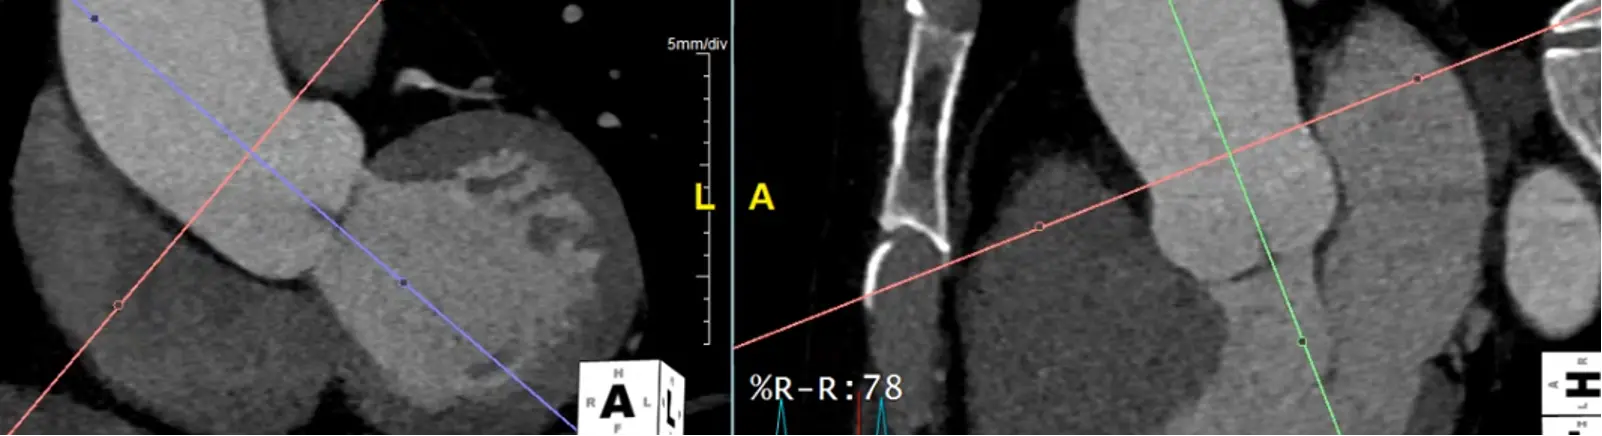

Measure at Sinotubular Junction

- Drag the lines to the sinotubular junction, i.e. where the sinuses and the tubule combine

- In the axial view, the âtrue short axisâ should be pretty close to appearing like a circle.

- đ Hit

Xto get the cross-hairs off.

Measure at the widest segment

- The widest segment (typically) is at the mid-aorta at the level of the main pulmonary artery (MPA)

- Same as above, drag your crosshairs to the desired level and adjust to be perpendicular to the artery wall in the coronal and sagittal views. Line up the blue/green line to be in the center/parallel to the long axis of the aorta at that level.

- In the axial view, the âtrue short axisâ should appear like a circle

Alt+Dto auto-measure- Right click and

Captureto add this to theSeries List

Measure aorta using âcandy caneâ view

- Rotate your cross hairs so you are cutting through both the ascending and descending thoracic aorta.

- Last step is to click the

MPRbutton at the top right and change it toMIP - Hit

Ctrl, hit the button down and drag sideways, you can increase/decrease the slab thickness. For example, this may allow you to capture the entire thickness of the aorta in different planes by manipulating the slab thickness. - Hit

Dto make measurements at different levels of the aorta. Provides a sanity check to make sure you didnât miss a larger/wider part of the aorta. - Right-click and select âCaptureâ to store this image with your measurements.